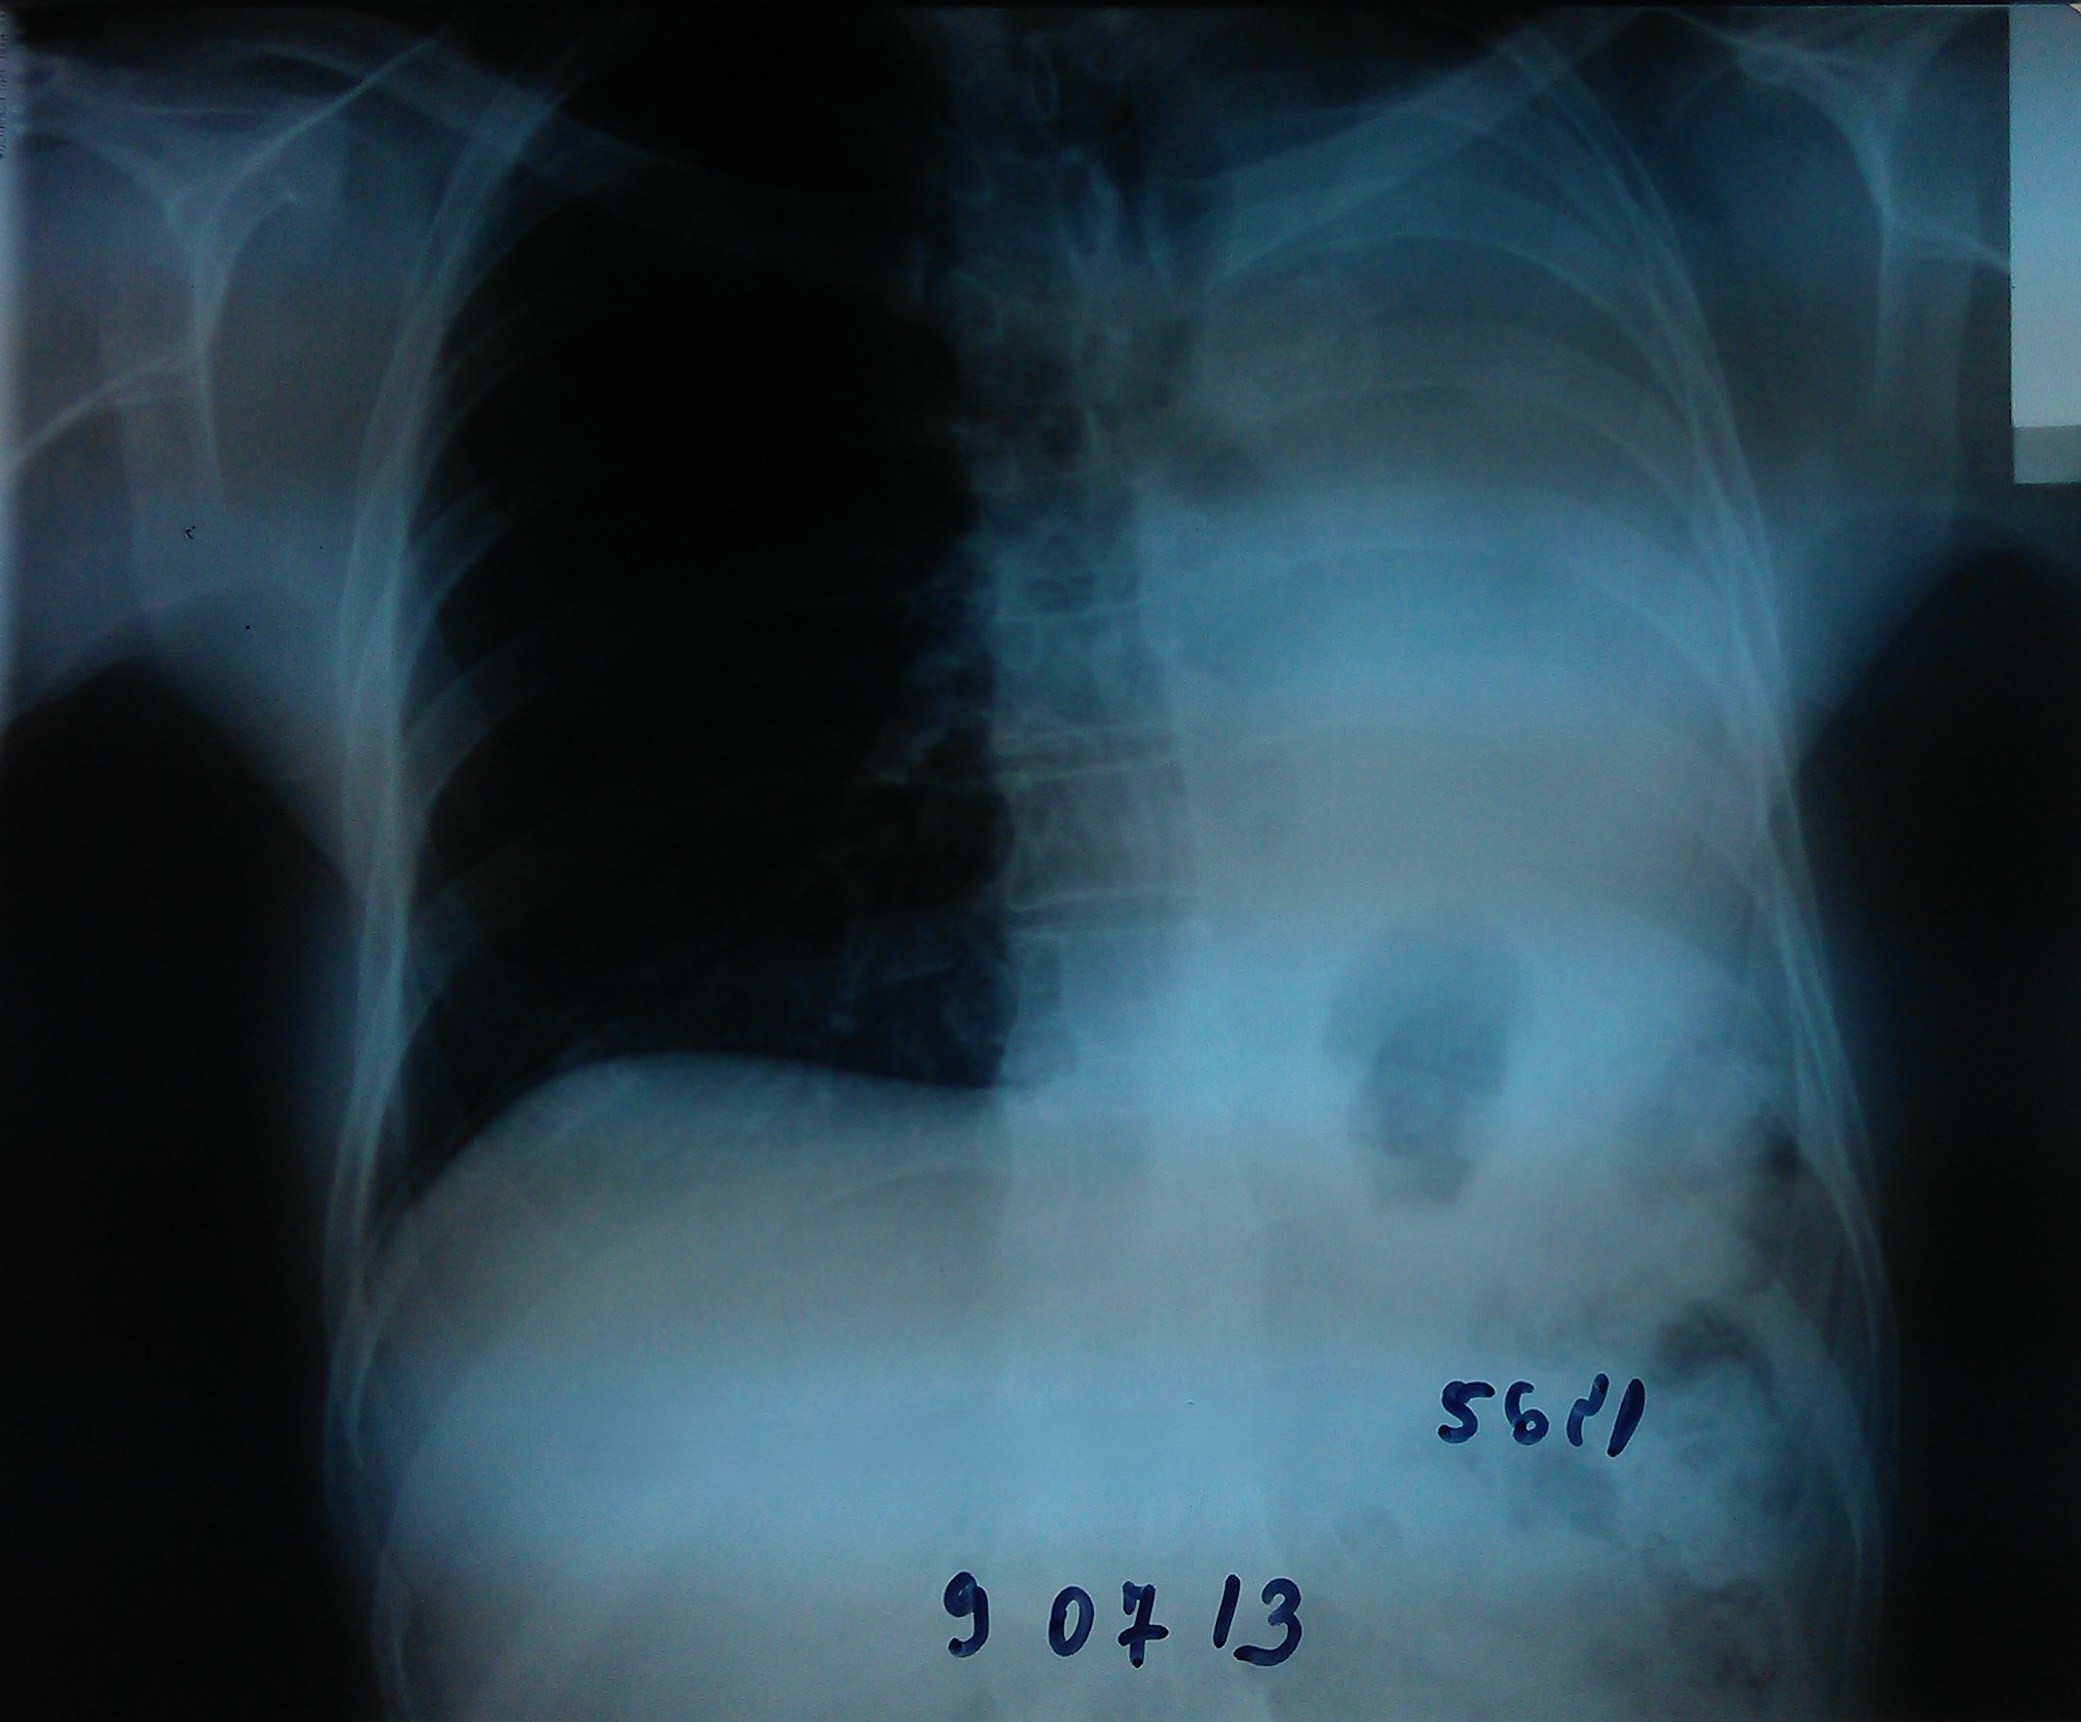

- გულმკერდის რენტგენოგრაფია სტენტირებამდე 10 დღით ადრე

აღინიშნება მარცხენა ფილტვის სრული ატელექტაზი